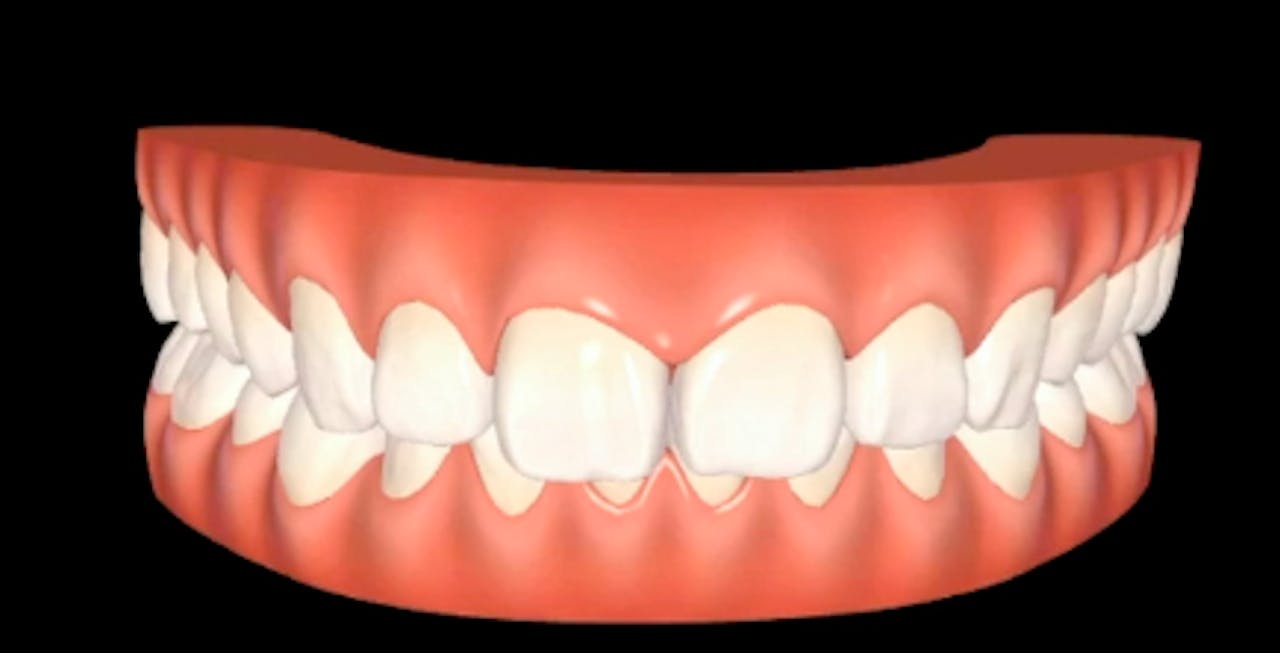

FEATURED VIDEOS gIDE Dental Institute Gide Dental Reviews Gide dental institute, los angeles, california. Dive deep (at your own pace) in a comprehensive online master class or residency with topics covering implant dentistry, esthetic dentistry,. Gide dental | 280 followers on linkedin. • 550+ clinical videos on web and app • new dental videos added. Clinical videos, expert interviews, live broadcasts over. Read 26 customer reviews of gide. Gide Dental Reviews.